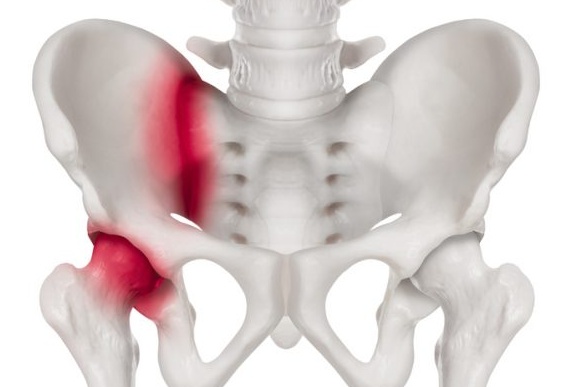

고관절 통증 증상(엉덩관절)은 오른쪽과 왼쪽의 골반과 넙다리뼈가 연결된 관절의 통증을 얘기합니다.고관절은 상체의 하중을 분산시키는 역할을 하며, 걷는 동안 체중의 3배, 달리는 경우 10배에 가까운 하중을 받습니다. 다른 관절과 마찬가지로 감당하기 어려운 충격이나 무게가 가해지면 고관절 통증 증상이 발생합니다. 퇴행성 고관절염, 대퇴골 골절, 대퇴골두 무혈성 괴사, 선천성 고관절 탈구 등이 대표적인 고관절 통증 질환입니다.

고관절은 골반 뼈 속에 공처럼 생긴 대퇴골의 골두가 맞물린 관절입니다. 대퇴골두는 다른 부위에 비해 혈액 순환 장애가 쉽게 올 수 있으며, 혈액 순환 장애는 대퇴골두 무혈성 괴사를 유발합니다. 뼈가 썩으면 몸의 하중을 정상적으로 견디지 못해 미세구조에 골절이 생기고, 심각한 통증이 발생합니다.

고관절 질환은 대부분 초기에는 통증이 나타나지 않거나, 통증이 적어 방치하기 쉽습니다. 평소 걷는 동안 불편함을 느끼고, 만성적이라면 언제부터 통증이 시작됐는지 정확히 기억하지 못합니다. 고관절 통증 증상은 위치상 발견이 어렵고 골반과 비슷한 위치에 있어, 골반 통증으로 오인하는 경우도 많습니다. 질환이 점점 진행되면서 사타구니나 둔부에 통증이 나타났습니다. 심한 경우에는 휴식을 취하고 있을 때도 통증을 호소하게 됩니다.

고관절 통증 증상은 주로 걸을 때 고관절이 위치한 사타구니 쪽에 나타나지만 사타구니는 물론, 고관절 통증 증상 등 신경줄기에 의해 연결된 무릎이나 허벅지 앞쪽까지 통증이 있습니다.